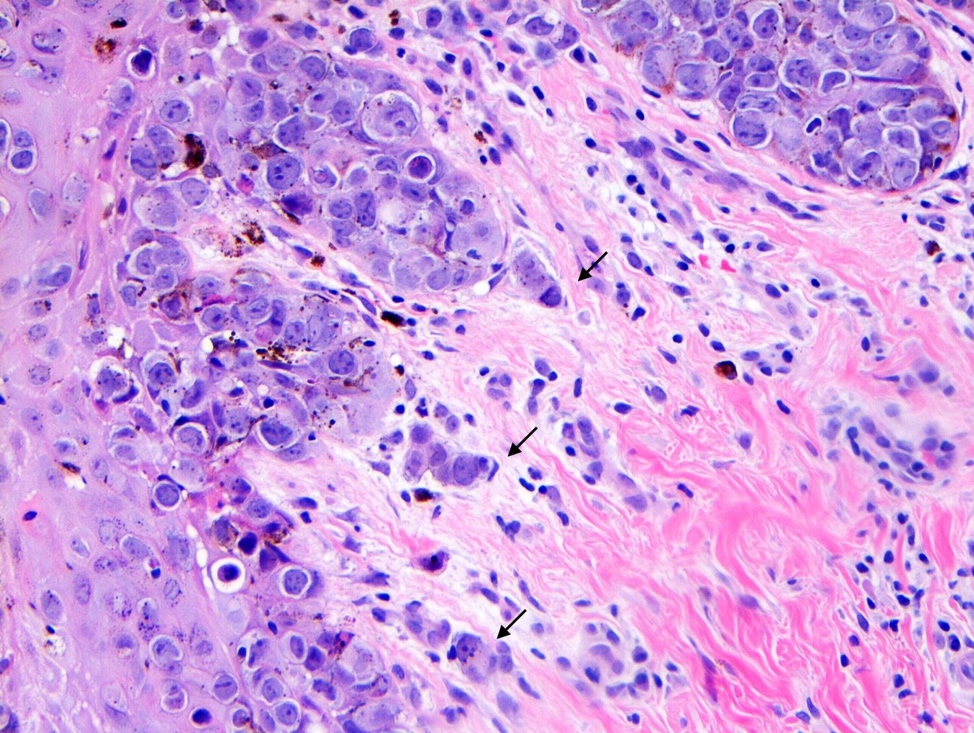

- Single cells or clusters of cells spread throughout the epidermis

- Cells have abundant pale cytoplasm, large irregular nuclei with prominent nucleoli

- Underlying dermis may have chronic inflammation

- Epidermis with hyperkeratosis and possibly ulceration

- Florid cases can show gland formation

- Paget cells may phagocytose melanin, mimicking melanocytes

- Underlying carcinoma is most commonly high grade invasive carcinoma of no special type (NST; 53 - 64%) or DCIS (24 - 43%) (Histopathology 2020;77:181)

Microscopic (histologic) images

Contributed by Anna Biernacka, M.D., Ph.D. and Mary Ann Gimenez Sanders, M.D, Ph.D.